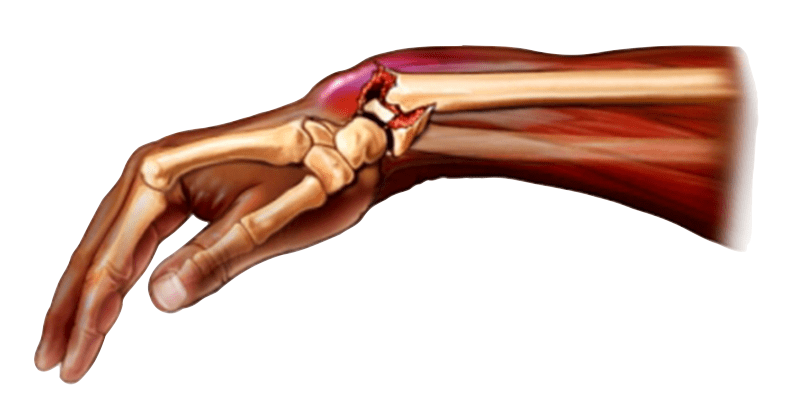

●  Fractura abierta: El hueso sobresale a través de la piel.

Es importante que la persona que ha sufrido una fractura realice la menor cantidad de movimiento posible, ya que puede causar más dolor o complicaciones. Se debe esperar a que lleguen profesionales médicos que sepan cómo actuar. En caso de que se trate de una fractura abierta, es necesario intervenir rápidamente para evitar que se infecte.